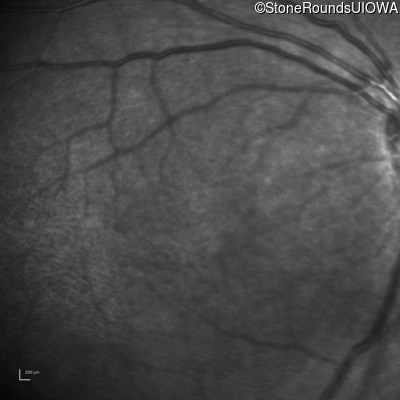

Infrared Fundus Photograph - Left - 10/40

Exemplar